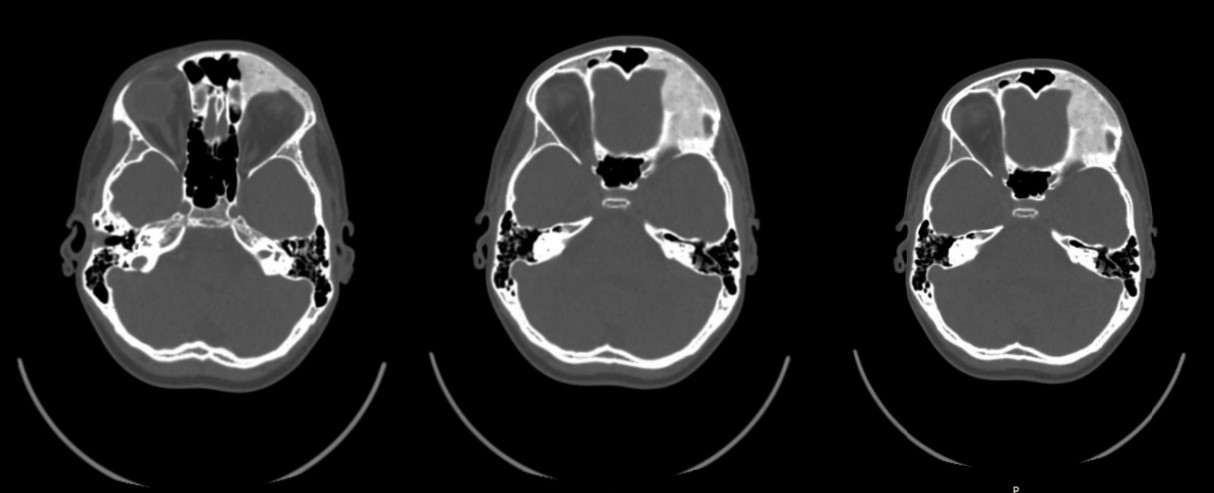

A 6 years old boy has been ill since 2016, when a forehead asymmetry was first noticed by his parents. After one month later, a CT scan was performed and a bone density formation was found in the area of the zygomatic arch of the frontal bone and in the area of the parietal bone on the left (Figure 8). The patient was admitted to the maxillofacial surgery department for treatment in RCCH on 2016 after consultation.

MSCT of the skull shows the affected osseous which is related to polyostotic craniofacial form of fibrous dysplasia in the left frontal bone and left parietal bone (25×40 mm in size and 7 mm in thickness). Locally, a bone density formation is visualized and palpated in these areas, originating from the bones (Figure 9).

Fig. 9. Preoperative axial CT image exhibiting characteristic homogeneously dense appearance of fibrous dysplasia involving the left frontal bone

A split auto-graft taken from the left parietal bone was remodeled to fit in the left frontal bone defect then fixed by mini-plate and mini-screw following by placing and fixing the internal cortical graft in the defect of the left parietal region (Figure 10).

Fig. 10. A split auto-graft. a — MSCT with three-dimensional reconstruction check-up, one day after the operation; b — Postoperative axial CT image